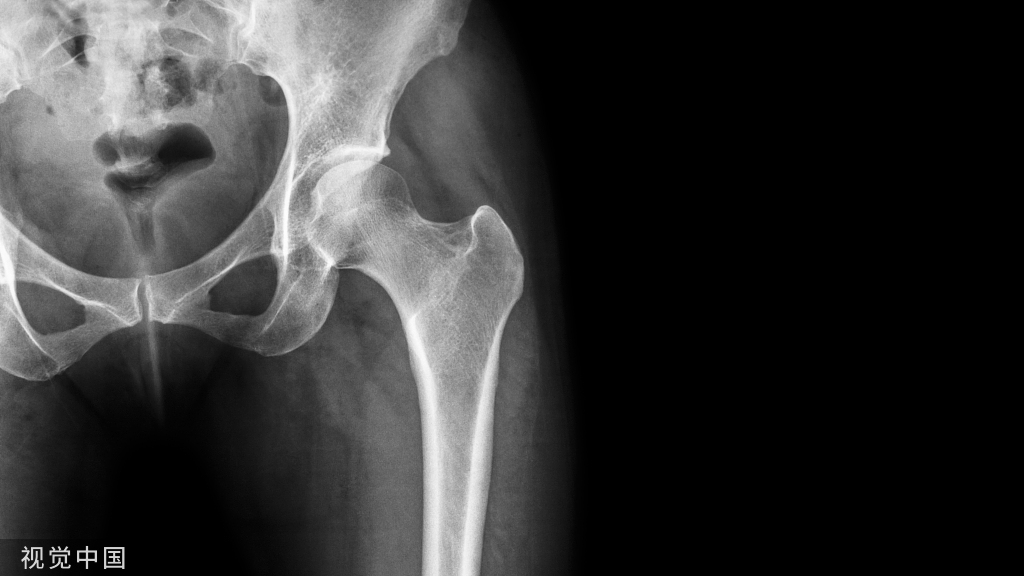

特别是对干骺端骨折,如股骨近端、股骨远端、桡骨远端等,将骨折靠近关节面端用锁定螺钉将钢板与骨块固定,后利用钢板原有解剖结构,将钢板固定至另一骨折端,达到骨折复位的目的。